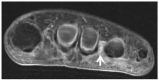

The terminology 'Morton's neuroma' may represent a simplification of the clinical condition as the problem may not be a benign tumour of the nerve, but neuropathic foot pain associated with the interdigital nerve.Foot and ankle pathomechanics leading to metatarsalgia, clinical examination and differential diagnosis of the condition and imaging of the condition, for differential diagnosis, are discussed.Nonoperative management is recommended initially. Physiotherapy, injections (local anaesthetic, steroid, alcohol), cryotherapy, radiofrequency ablation and shockwave therapy are discussed.Operative treatment is indicated after nonoperative management has failed. Neuroma excision has been reported to have good to excellent results in 80% of patients, but gastrocnemius release and osteotomies should be considered so as to address concomitant problems.Key factors in the success of surgery are correct diagnosis with recognition of all elements of the problem and optimal surgical technique. Cite this article: EFORT Open Rev 2019;4:14-24. DOI: 10.1302/2058-5241.4.180025.